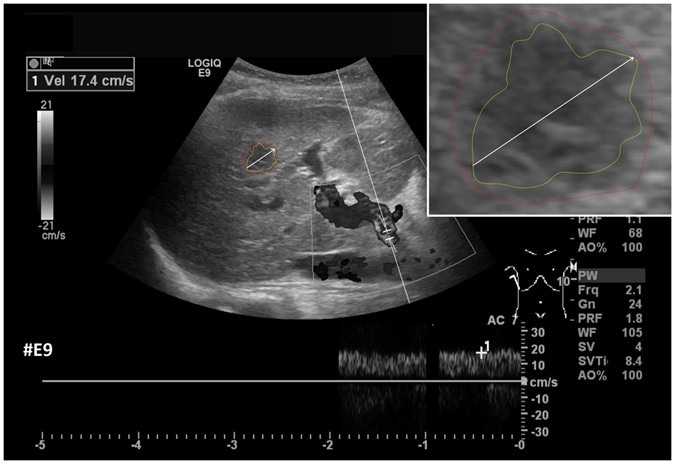

After the initial setup of the algorithm parameters using liver metastases with predefined echo pattern, we evaluated the algorithm using a set of 40 images of 24 patients with pancreatic cancer liver metastases from clinical routine. In total, 37 different metastases have been segmented in random order. Three metastases have been segmented with a different image zoom. The selection reflected the general echogenicity distribution of pancreatic cancer metastases, with 31 of the 37 metastases being hypoechoic, 5 isoechoic and one hyperechoic compared to the surrounding liver tissue. The images have not been previously segmented with the proposed algorithm before. Initially, the operator performed a manual segmentation of the metastases and then measured the maximal diameter in a separate window. Subsequently, the semi-automatic segmentation was performed. Figure 11 presents an overlay of the three measurements. The red outline represents the manual segmentation including the white arrow representing the manually drawn maximum diameter. The yellow line represents the result of the semiautomatic segmentation. The operator spent a total of 26 minutes for the manual measurements of the 40 metastases and 18 minutes using the semiautomatic segmentation. This results in a mean segmentation time of 27 seconds per metastasis using the semi-automatic method and of 39 seconds using the manual method. Comparison of the two methods revealed an average Dice Score (DSC)36 of 84.76 ± 5.08% and an average Hausdorff Distance (HD)37 of 12.58 ± 5.74 pixel (Table 1). The DSC is the agreement between two binary volumes and is calculated as follows:

Comparison of manual and semi-automated segmentation of a pancreatic cancer liver metastasis. The native image with a zoomed view of the metastasis is presented (white box). The red outline represents the manual segmentation including the white arrow representing the manually drawn maximum diameter. The yellow line represents the result of the semi-automatic segmentation.